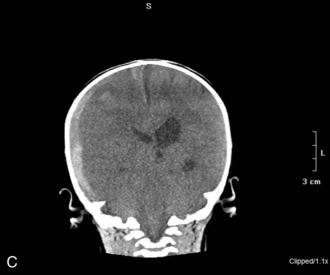

The patient with an SAH may experience a sudden onset of a severe headache (the most common symptom and present in nearly all cases), emesis, syncope, meningismus, and photophobia. These symptoms are associated with a rapid rise in ICP. Left untreated, the child will progress to coma and possibly death. Although spontaneous SAHs can arise from a variety of sources, including aneurysms, coagulation disorders, and small artery ruptures, trauma remains the leading cause of an SAH in children. CT scans performed within 48   hours of a hemorrhage will detect the vast majority of subarachnoid hemorrhages. The blood will appear as a white, hyperdense area in the subarachnoid spaces (see Fig. 11–12, B and C).

Throughout the child's care, the nurse must be alert for signs of increased ICP (see Increased Intracranial Pressure). The sudden appearance of irritability, confusion, lethargy, and pupil dilation must be reported to a physician or other on-call provider immediately. Emergency acute management of sudden increases in ICP requires immediate intervention with support of the airway, oxygenation, and ventilation and administration of mannitol (0.5-1   gm/kg IV) or 3% saline (3-5   mL/kg IV bolus), or both. A CT scan is typically performed to detect any mass lesion requiring surgical intervention; the CT scan also will enable the evaluation of cerebral edema (see Fig. 11-12).20